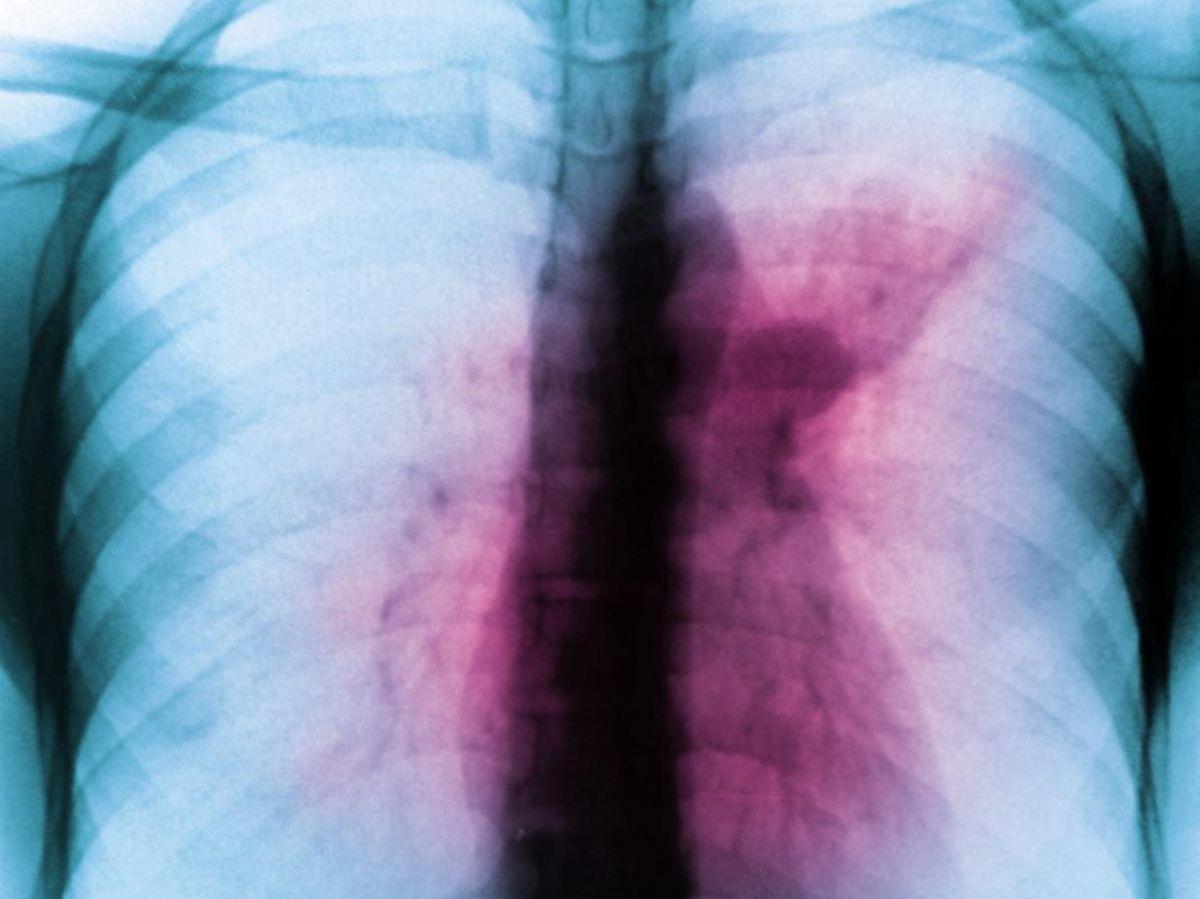

Africa-Press – Côte d’Ivoire. La tuberculose, fléau du 19e siècle, pourrait-elle devenir le nouveau fléau du 21e siècle ? Cette maladie infectieuse, qui affecte principalement les poumons, n’a jamais été éradiquée. Sa progression a fortement ralenti grâce notamment au vaccin BCG (vaccin bilié de Calmette et Guérin). Mais ce vaccin n’empêche pas entièrement l’infection et la transmission de la bactérie Mycobacterium tuberculosis, responsable de la maladie.